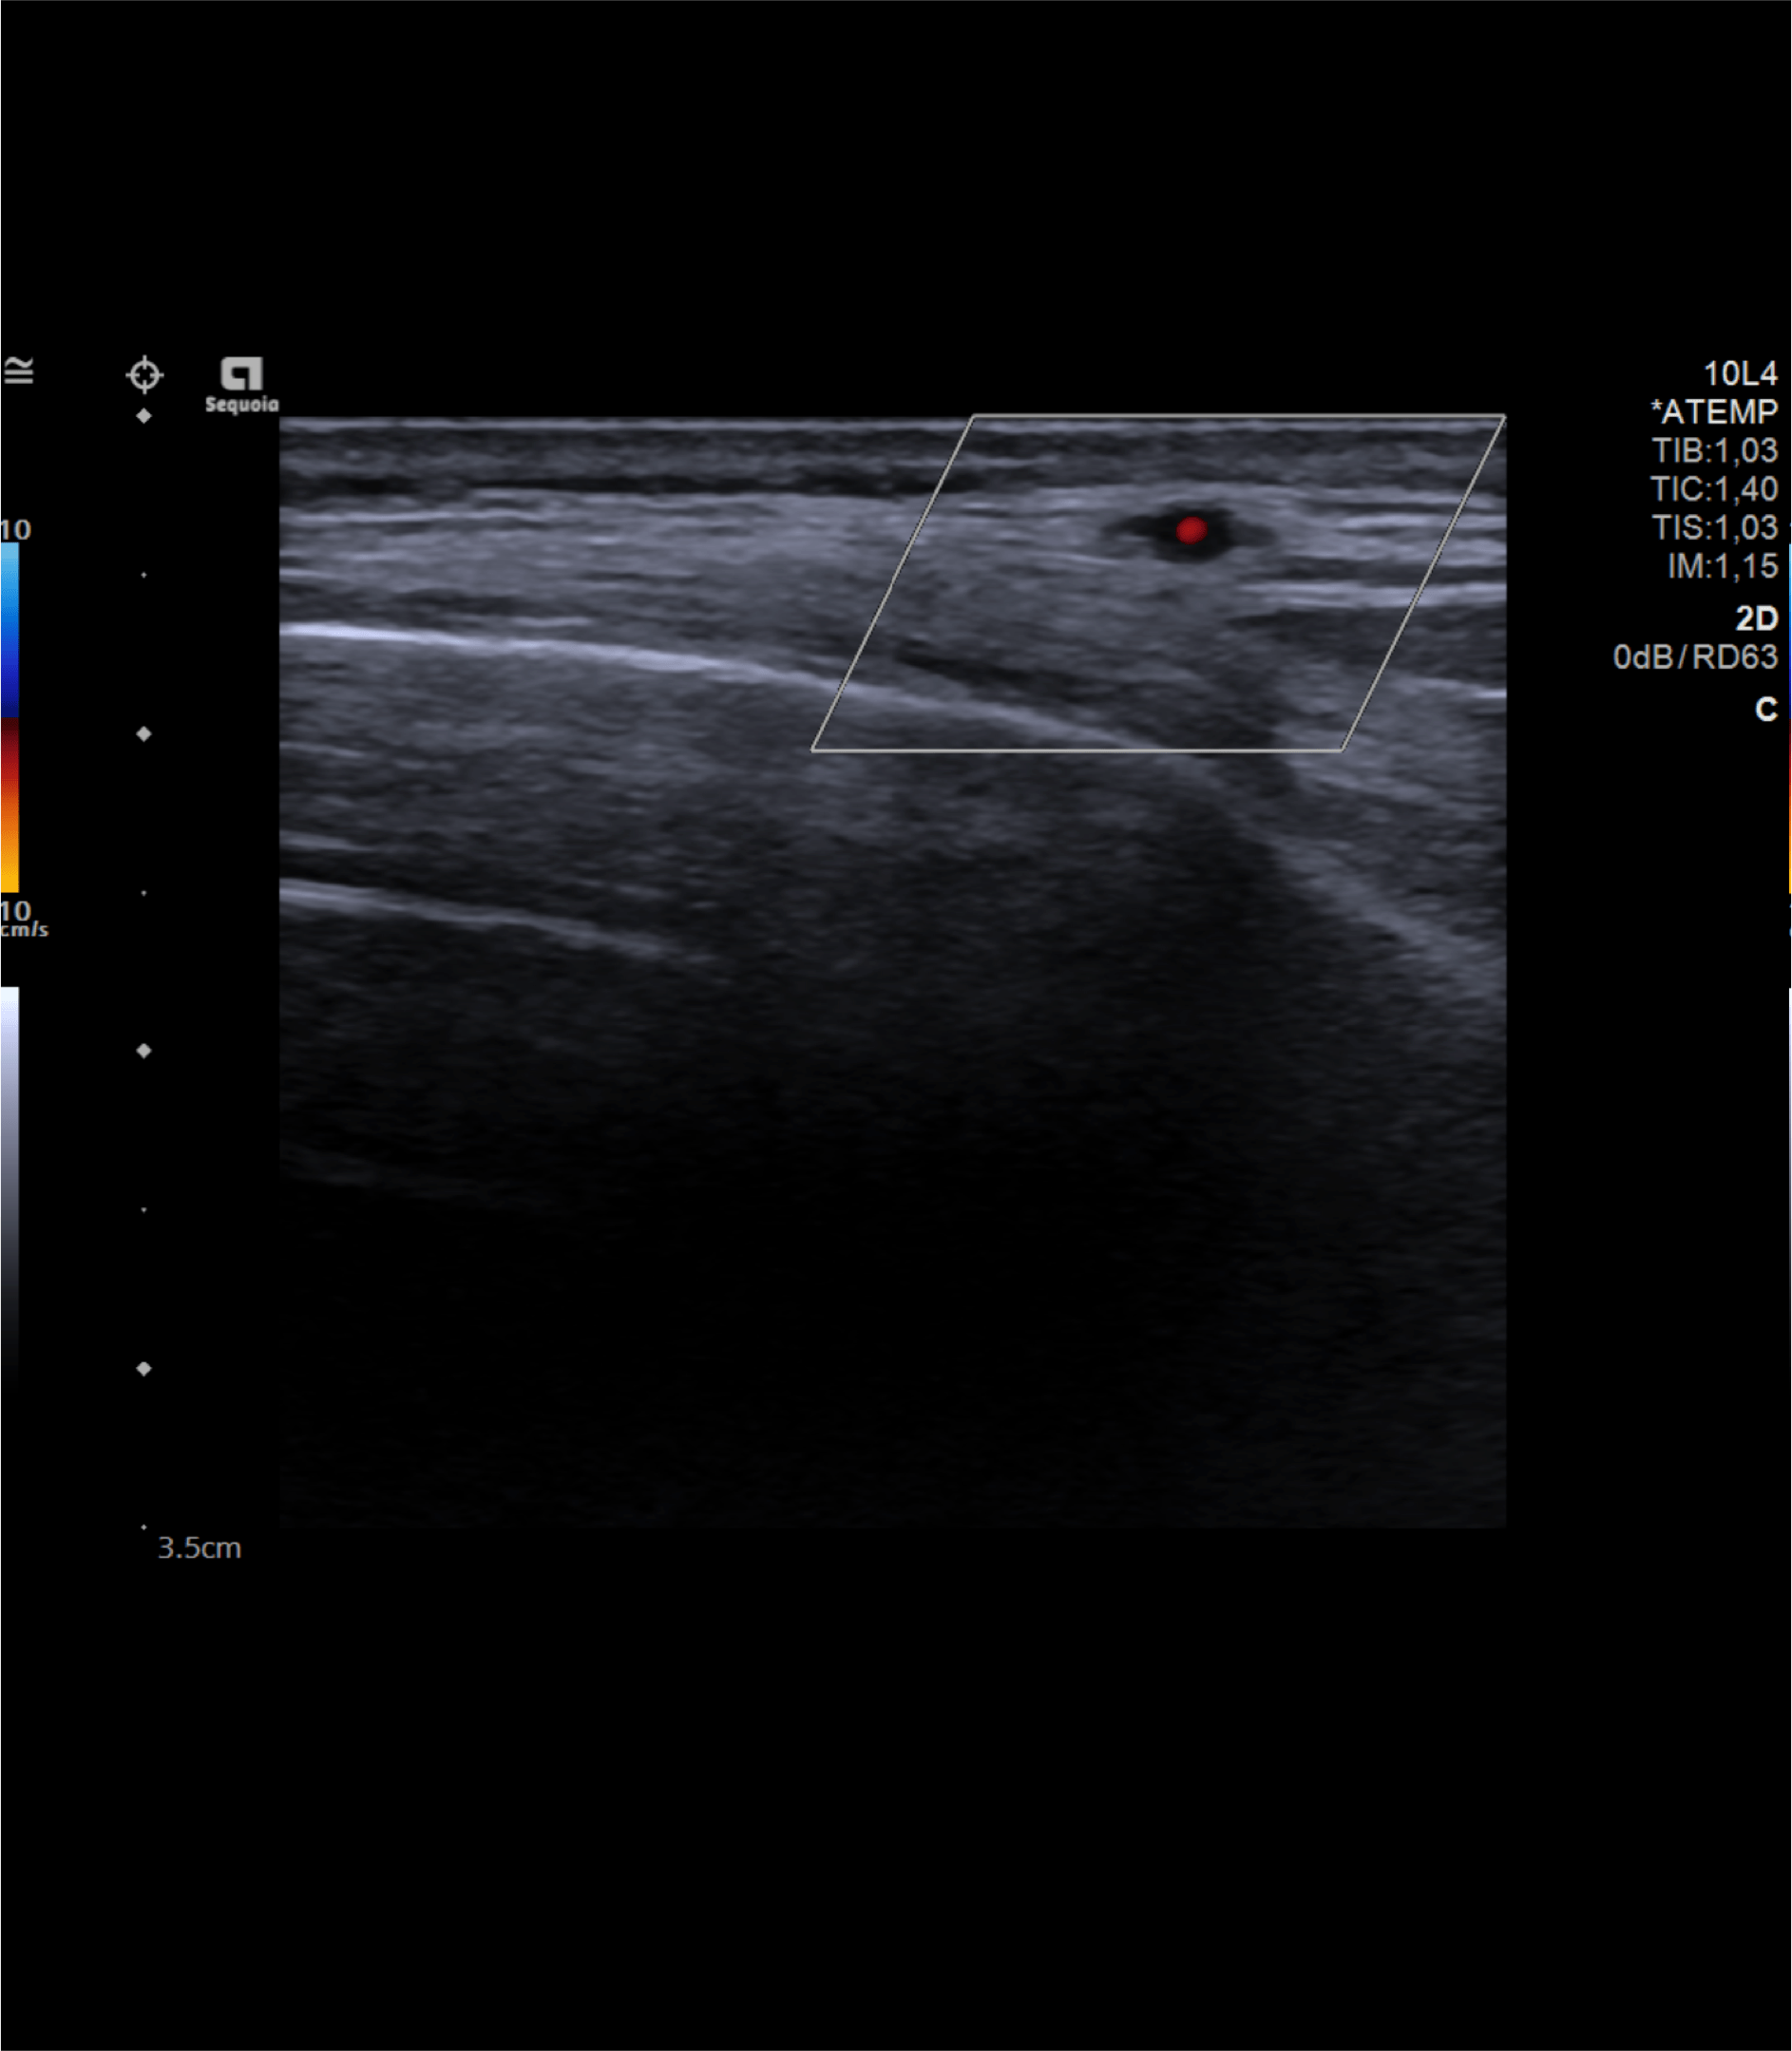

Realizamos una ecografía centrada en la zona temporal derecha del paciente.

Hallazgos ecográficos

Observamos engrosamiento parietal de arteria temporal iderecha con halo hipoecoico periférico, disminución de su calibre y cambios inflamatorios asociados.

Ante la sospecha clínica de arteritis de la temporal decidimos realizar la ecografía en nuestro Centro de Salud.

El paciente ingresó a cargo de Neurología donde solicitaron ecografía modo Doppler de ambas arterias temporales y RMN cerebral. Además, fue valorado por Oftalmología.

En conclusión, ante un paciente de edad avanzada y síntomas que hagan sospechar la presencia de una arteritis de la temporal debe considerarse la realización de una ecografía modo Doppler para su diagnóstico y así evitar el retraso del diagnóstico definitivo mediante biopsia.